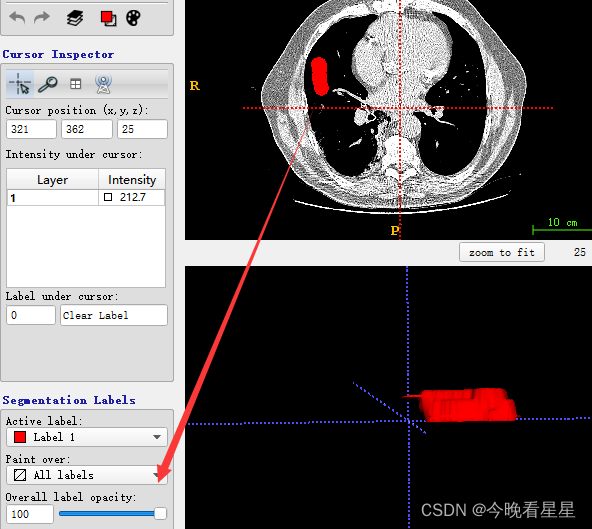

Active Label为激活的标签,表示当前使用的标柱类型,此时选择label 1为红色,说明使用红色进行标注paint Over为允许标注的范围,All labels允许对所有的标签进行标注,包括覆盖之前的标注;All visiable label是对所有可见的标签进行标注,如图,红色所在的位置则不能标注,

paint over续:使用Active Label=Label1; paint Over=Clear Label标注时,只允许对没有标注的区域标注,如图,同样的,如果paint over=Label1(red), active label = label3则蓝色只能在红色上标注